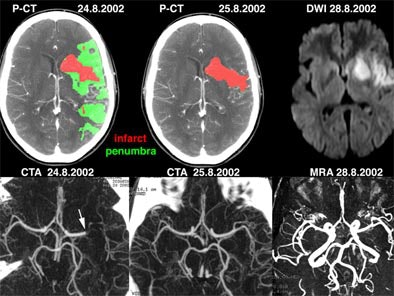

![]() |

| Above: a) Admission perfusion CT demonstrates mixed infarct and penumbra in the left sylvian territory in a patient with a right hemisyndrome, whereas b) CT angiography (CTA) relates it to an occlusion at the left M1-M2 junction (arrow). The patient underwent intravenous thrombolysis and his clinical condition evolved favorably. Twenty-four hours after admission, d) follow-up CTA features a recanalization of the left sylvian artery, later confirmed on f) MR angiography (MRA). c) Follow-up perfusion-CT shows an almost complete resolution of the penumbra, afforded by the early arterial recanalization. The final perfusion CT infarct has progressed only in a very limited fashion compared to the admission perfusion CT infarct; its extent closely correlates with the abnormality on e) delayed DWI trace image. Images courtesy of Dr. Max Wintermark. |